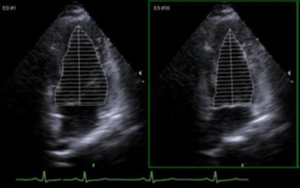

syngo 自动左心脏

- 自动描记心脏的心尖四腔和心尖二腔视图上心舒期末期和心缩期末期影像的左心室心内膜边界的轮廓

- 生成心舒期末期容积和心缩期末期容积、射血分数及心率的计算数据和测量结果